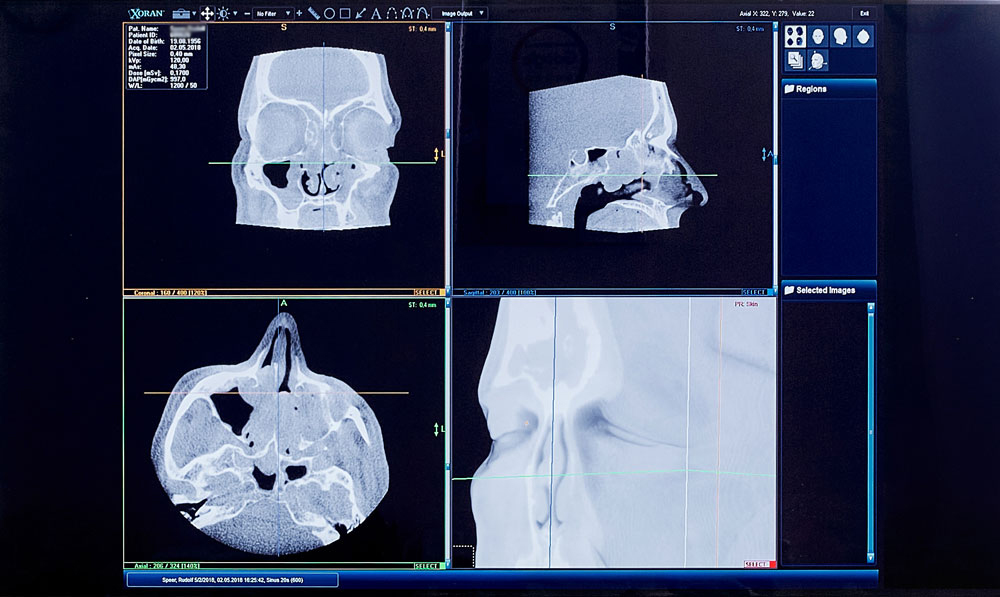

Die digitalen Volumentomographie (DVT), eine der neuesten Entwicklungen der bildgebenden Diagnostik, ist eine hochauflösende Schnittbild-Diagnostik mit wenig Strahlenbelastung. Sie stellt die kleinsten Knochenstrukturen des Schädels zwei- und dreidimensional dar. Dies hat entscheidende Vorteile bei der Untersuchung von Zähnen, Nasennebenhöhlen und Mittelohren. Die Genauigkeit liegt bei bis zu 0,2 mm.